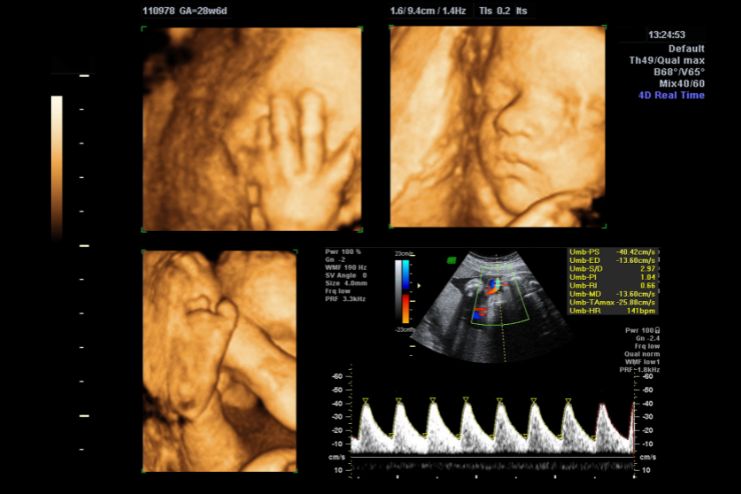

For many parents, hearing their baby’s heartbeat for the first time is magical. But imagine seeing your baby yawn, stretch, or even suck their thumb while still in the womb. That’s exactly what a 4D ultrasound offers. It is a moving, real-time view of your little one’s world, complete with adorable facial expressions and sweet little gestures.

Unlike the old-school 2D ultrasounds or the inanimate 3D scans, a 4D ultrasound is more like having a personal movie night with your baby. It’s more than a medical visit; it’s an experience that many expectant families hold dear forever.

- 3D ultrasound provides depth to those pictures, presenting you with a still, life-like image of your baby’s face or body in three dimensions.

- 4D ultrasound goes one step further. It’s actually 3D in action, taking ongoing video of your baby wriggling around inside your womb in real-time.

While 4D scans will sometimes pick up on abnormalities, they are generally non-diagnostic and performed for bonding and keepsake reasons. Imagine them as your baby’s first movie.

What You’ll See on the Scan (And What You Might Not)

With favorable conditions, you may see:

- Your baby’s facial expressions, such as smiling, frowning, or yawning

- Thumb sucking, hiccuping, or stretching

- Soft movements such as waving or kicking

These moments are usually amazing for expectant mothers and fathers, offering a lovely glimpse into their baby’s personality even before birth.